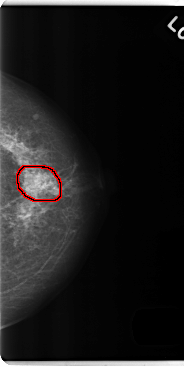

C_0186_1.RIGHT_MLO

FILE: C_0186_1.RIGHT_MLO.OVERLAY

TOTAL_ABNORMALITIES 1

ABNORMALITY 1

LESION_TYPE CALCIFICATION TYPE PLEOMORPHIC DISTRIBUTION SEGMENTAL

LESION_TYPE MASS SHAPE IRREGULAR MARGINS ILL_DEFINED

ASSESSMENT 5

SUBTLETY 5

PATHOLOGY MALIGNANT

TOTAL_OUTLINES 1

BOUNDARY